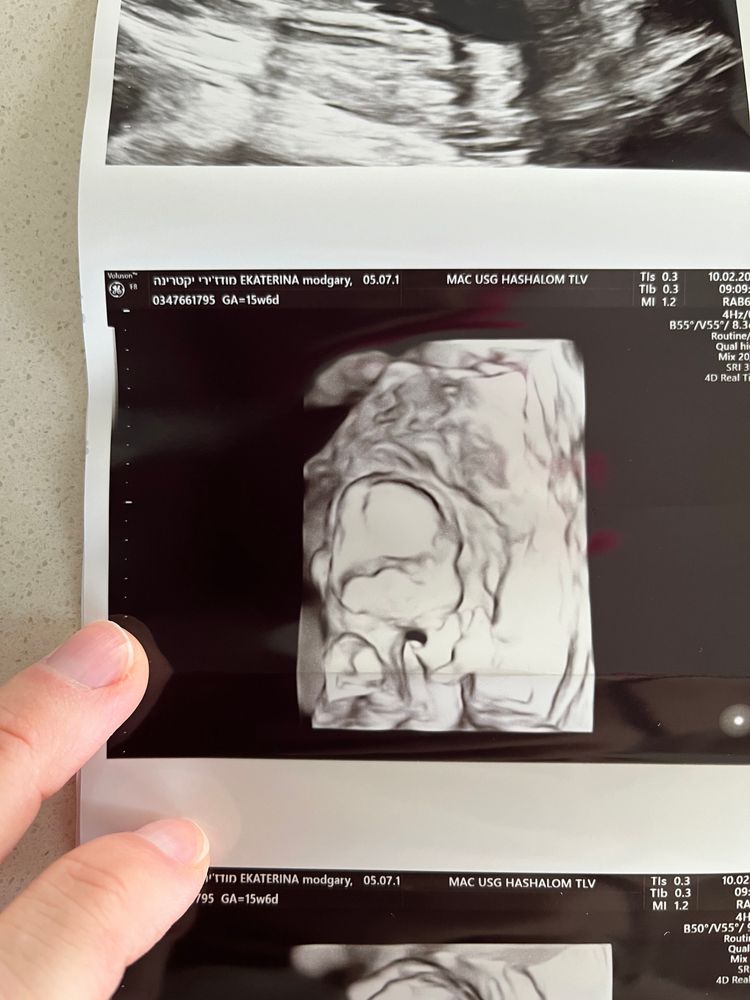

УЗИ 15 недель

УЗИ, КТГ, доплерВот мы и попали на скрининг систем, вроде бы все хорошо

Доктор несколько раз говорил, посмотрите какие губы, а я их даже на последнем 3D снимке вижу.

написал нам пол на бумажке и вчера мы узнали, что у нас будет девочка